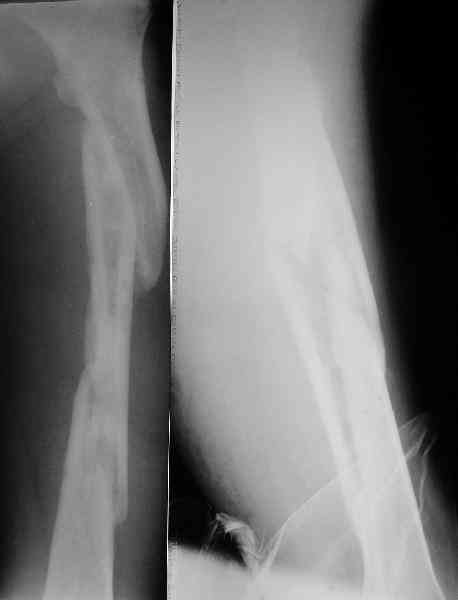

Надо делать чрескожную подвертельную остеотомию, чтобы получился открытый клин. Проблемы будут и с формированием канала, надо развертки типа наших. Был как-то похожий случай, сделали одномоментно, сняли аппарат 5-месячый на столе, заштифтовали с подвертельной остеотомией (в приложении).